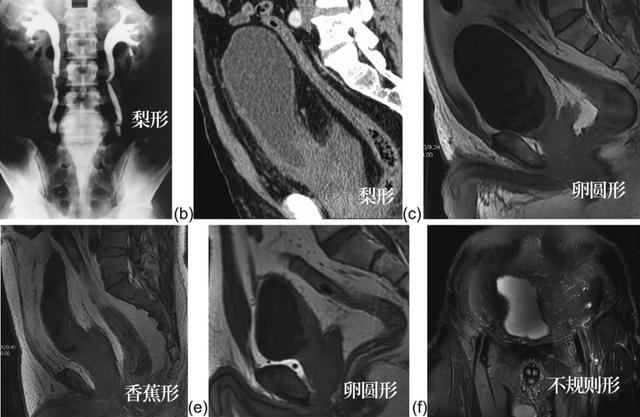

膀胱形态:据文献报道,梨形和香蕉型膀胱对 PL 的诊断特异性为 100%,三角形为 92%,不规则形为 80%,卵圆形最低,为 28%。

膀胱精囊角>75% 诊断 PL 特异度为 100%。

直肠形态学(RMI):CD/EF。AB 是横穿正中矢状面精囊基底部的水平线;CD 是直肠的前后长度;EF 是轴位直肠的横向直径。CD/EF=1.25 诊断 PL 特异度为 96%。